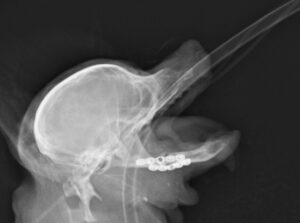

重度の歯周病で両側の下顎の病的骨折をしているワンちゃんが来院されました。悪い歯の抜歯と下顎のプレート固定(TITAN LOCK1.2mm使用)で対応しました。退院後しっかりご飯が食べられるようになりました。よかったね。